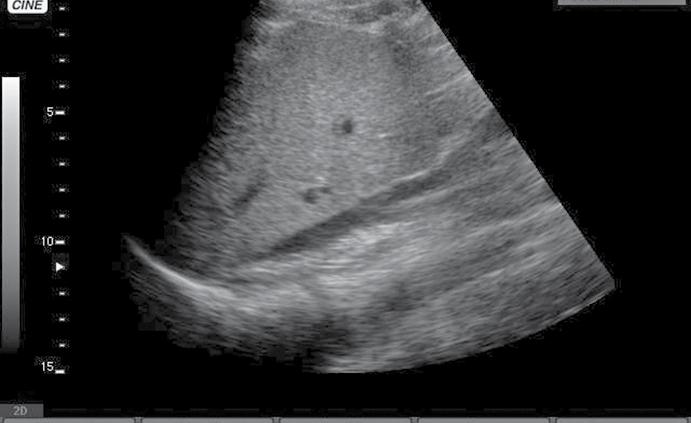

• aprecierea mărimii ventriculului stâng comparativ cu cel drept – identificarea unei supraîncărcări a ventriculului drept, cu suspiciunea de cord pulmonar acut (fig.5) și necesitatea de administrare de trombolitic pentru trombembolism pulmonar;

Fig.9. Pseudoanevrism aortic Fig.10. Anevrism aortic trombozat Fig.11. Tromboză venă femurală dreaptă

Fig.5. Secțiune subxifoidiană. Cord drept dilatat